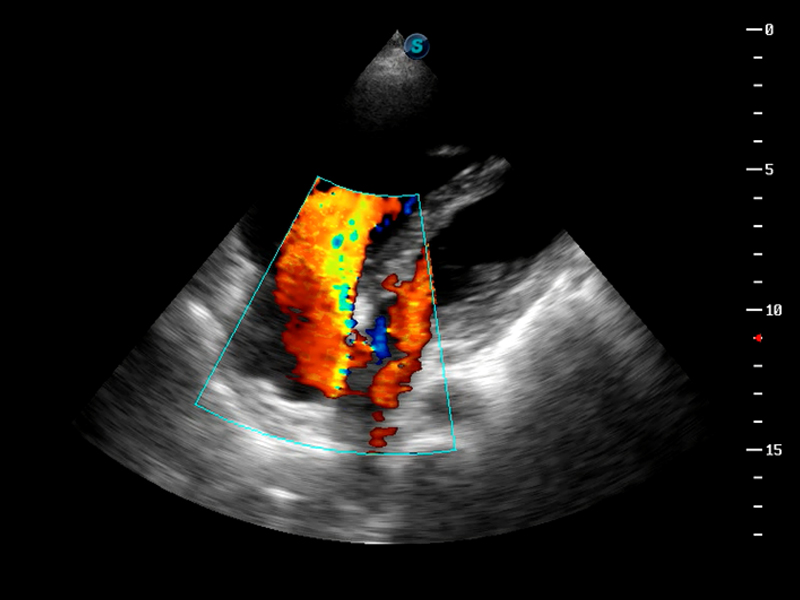

S9便携式彩色多普勒超声诊断仪是1xBET研发的高端便携彩超设备,外观设计新颖、产品性能卓越。S9在便携超声领域采用了突破传统的触摸屏交互设计,并以先进的软件硬件技术和设计理念,为您带来清晰的图像质量、稳定的工作性能和便捷的操作体验。

AutoC智能血流追踪